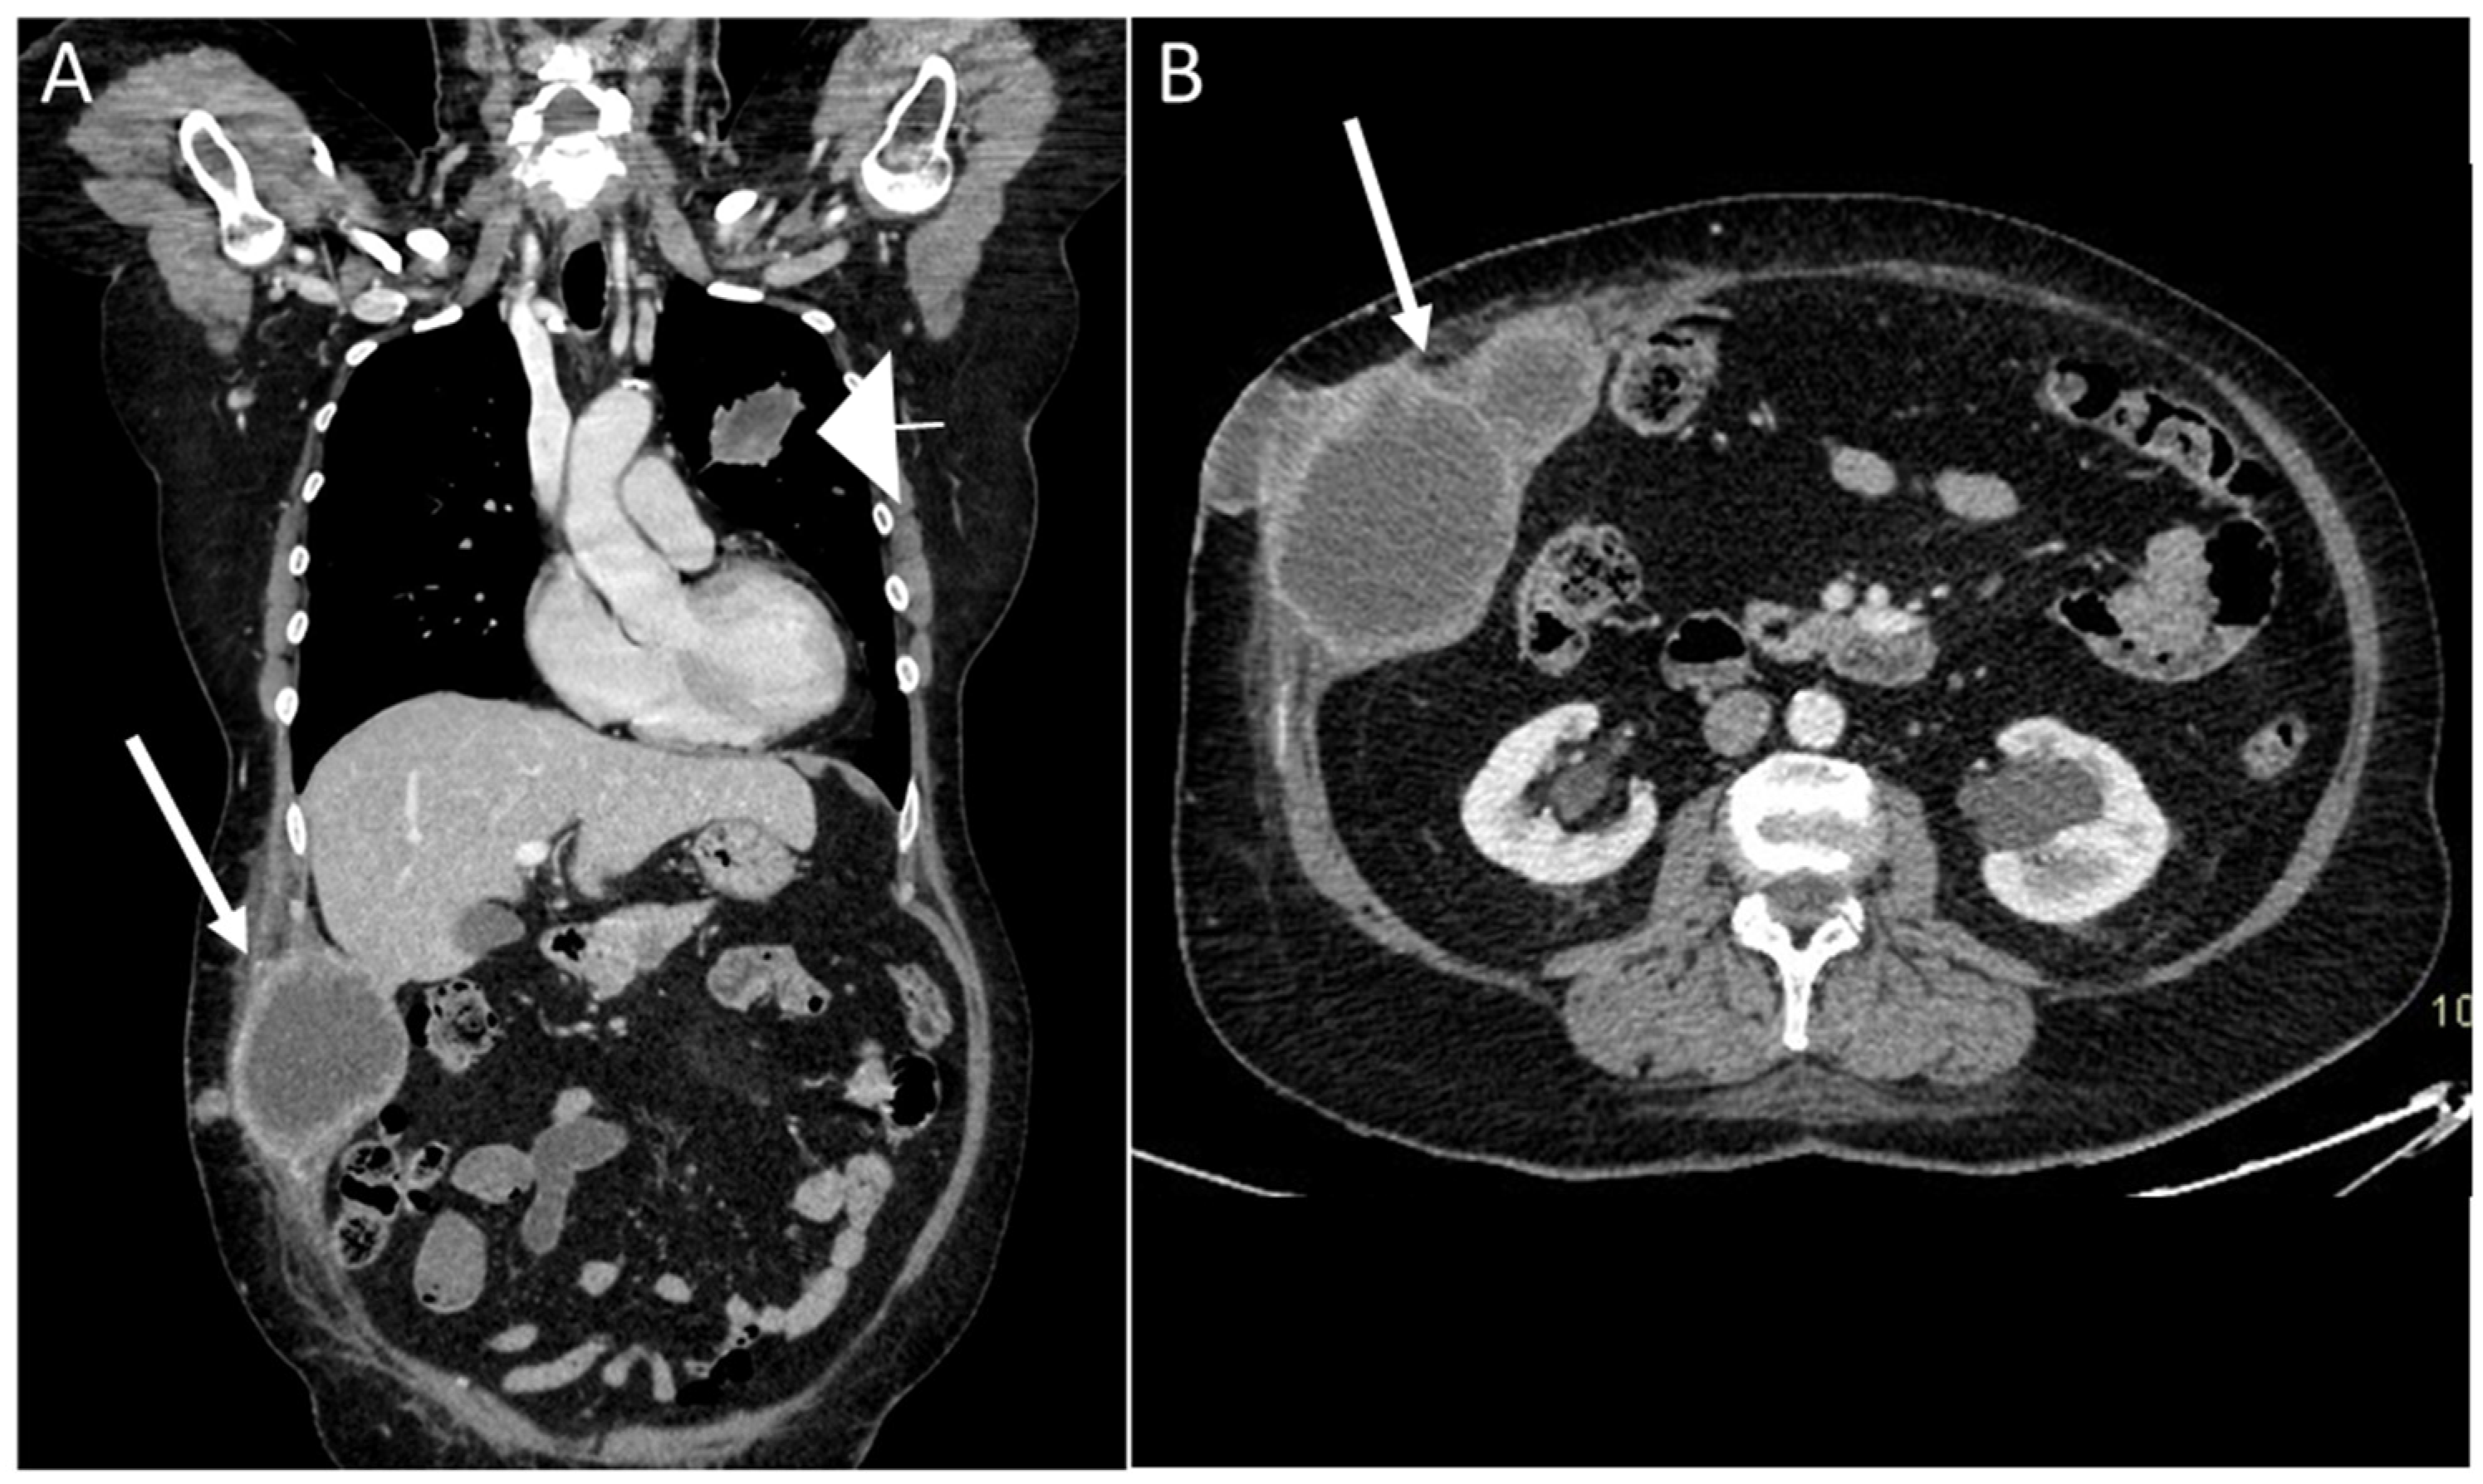

- Desmoplastic Small Round Cell Tumor (DSRCT): rare, highly aggressive sarcoma of adolescents, which primarily involves the serosal surfaces of the abdominal cavity infiltrating the abdominal wall [30,31,32]. Classic findings include bulky multiple, hypoattenuating, soft-tissue masses, with omental, serosal, and rectovesical involvement [31,32] and typical punctate or amorphous calcifications [32]. Modest heterogeneous enhancement is seen on arterial phase, without prolonged enhancement or portal washout [31,32] (Figure 10). On MR, DSRCTs are heterogeneously iso- to-hypointense on T1-w images, with hyperintense foci due to intratumoral hemorrhage [32].